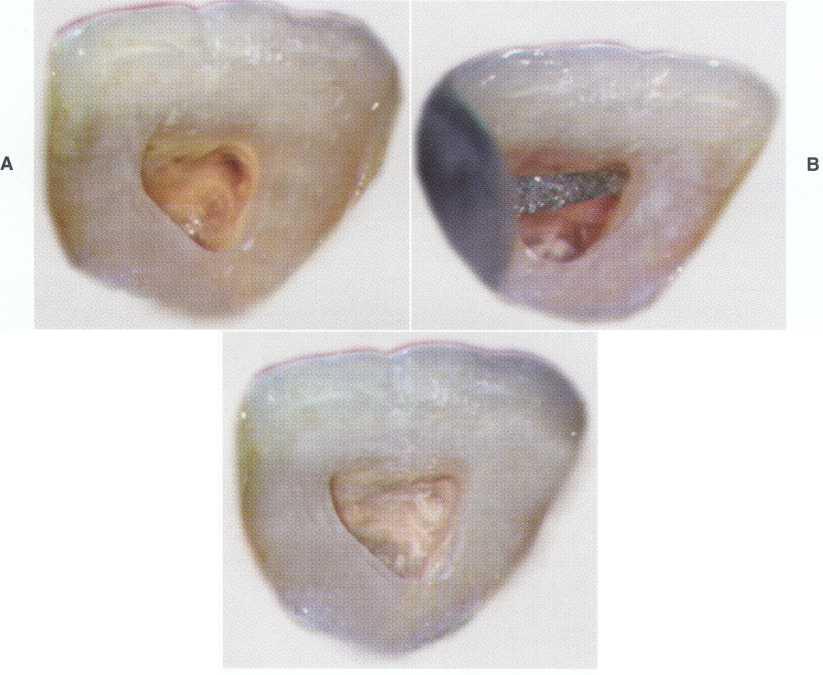

Visual inspection of the soft tissues should include an assessment of color, contour, and consistency. Localized redness, edema, swelling, or a sinus tract can indicate inflammatory disease. Examination of the hard structures may reveal clinical findings such as developmental defects, caries, abrasion, attrition, erosion, defective restorations, fractured cusps, cracked teeth, and tooth discoloration (Figure 1-1).

FIGURE 1-1

A 32-year-old woman presents for treatment of spontaneous pain that keeps her awake at night. She relates a history of orthodontics and a frenectomy as an adolescent, as well as traumatic injury to the maxillary anterior area during a basketball game. Clinical examination reveals normal-appearing soft tissues, scar formation consistent with location of the suture placed after the frenectomy, and discoloration of the maxillary left central incisor, tooth #9.